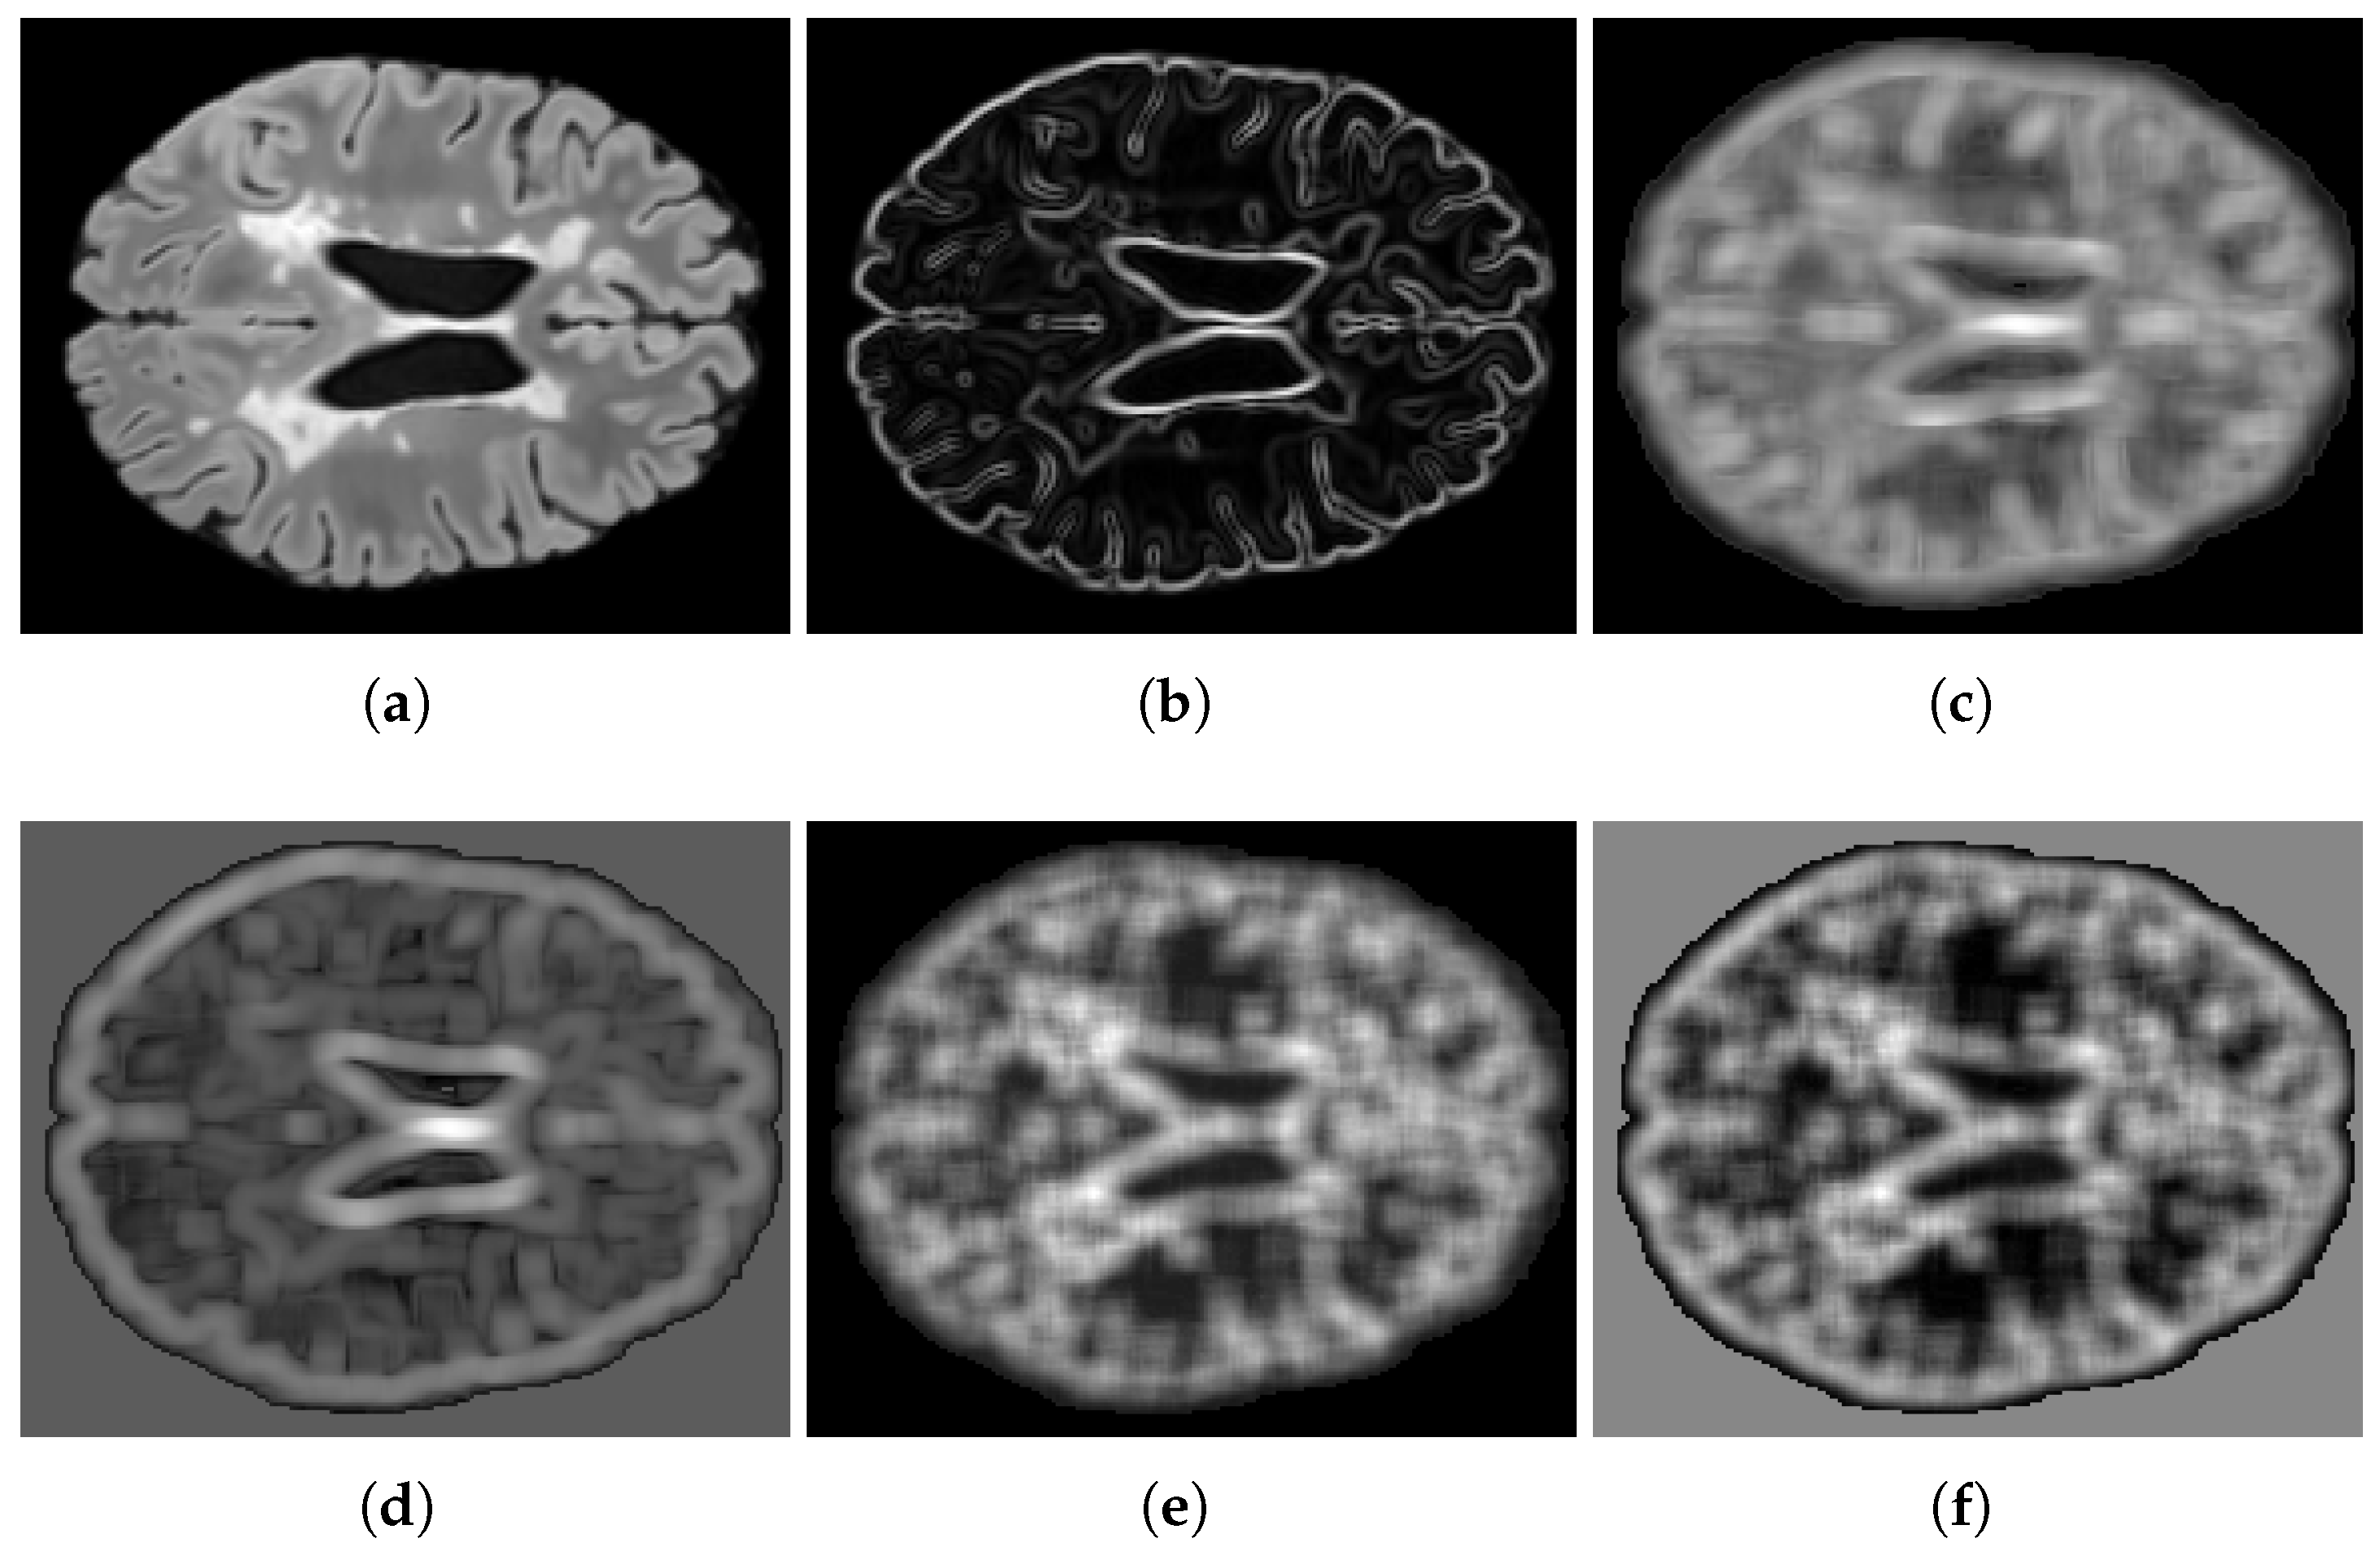

Figure 3. Comparison of distance maps. The figure shows (a) a segmentation mask G and different distance maps: (b) G D T M , (c) G S D F , and (df) G M D M λ maps with different values of λ : (d) λ = 0.5 , (e) λ = 1.5 , and (f) λ = 2.5 .

The parameter λ modulates how the penalty scales with respect to the distance map. Specifically, G M D M ( p ) λ acts as a weighting factor that increases or decreases the contribution of a voxel according to its distance from the nearest boundary of the opposing class. When λ > 1 , voxels located farther from the class boundary are penalized more heavily, enforcing sharper separation between regions. Conversely, when 0 < λ < 1 , the weighting function is compressed, leading to a milder penalty on distant voxels and a relative emphasis on those closer to the boundary. Figure 3d–f illustrate the Mahalanobis distance maps produced by Algorithm 1 at varying λ values. In contrast to the traditional DTM (Figure 3b) and SDF (Figure 3c) maps, our proposed maps allow for a larger range in the distances between voxels near the boundary due to the incorporation of texture features in the distance calculation. From the perspective of classification errors, the term G M D M ( p ) penalizes voxels that, given their true class G ( p ) , lie in the spatial vicinity of the opposite class. This penalty is proportional to the degree of dissimilarity, which tends to be higher for voxels outside lesions compared to voxels inside them. Consequently, the loss formulation biases the optimization toward reducing false positives more strongly than false negatives, as misclassified voxels outside the lesion area (FP) incur higher costs relative to those inside (FN).